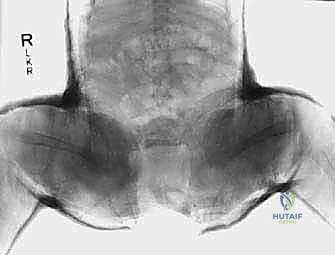

2. الأشعة السينية (X-Rays)

عندما يبلغ الطفل 6 أشهر فما فوق، تبدأ مراكز التعظم في الظهور في رأس الفخذ. في هذه المرحلة، تصبح الأشعة السينية ضرورية وأكثر دقة من الموجات فوق الصوتية.

يقوم الأستاذ الدكتور محمد هطيف بتحليل دقيق للأشعة السينية، حيث يرسم خطوطاً وهمية (مثل خط هيلجينراينر وخط بيركين) لتحديد موقع رأس الفخذ بدقة، وقياس "مؤشر الحُق" (Acetabular Index) لمعرفة مدى ضحالة التجويف. هذه القياسات حاسمة لتحديد ما إذا كان الطفل يحتاج إلى جراحة أم لا.